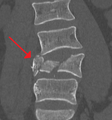

A burst fracture of L4 as seen on CT